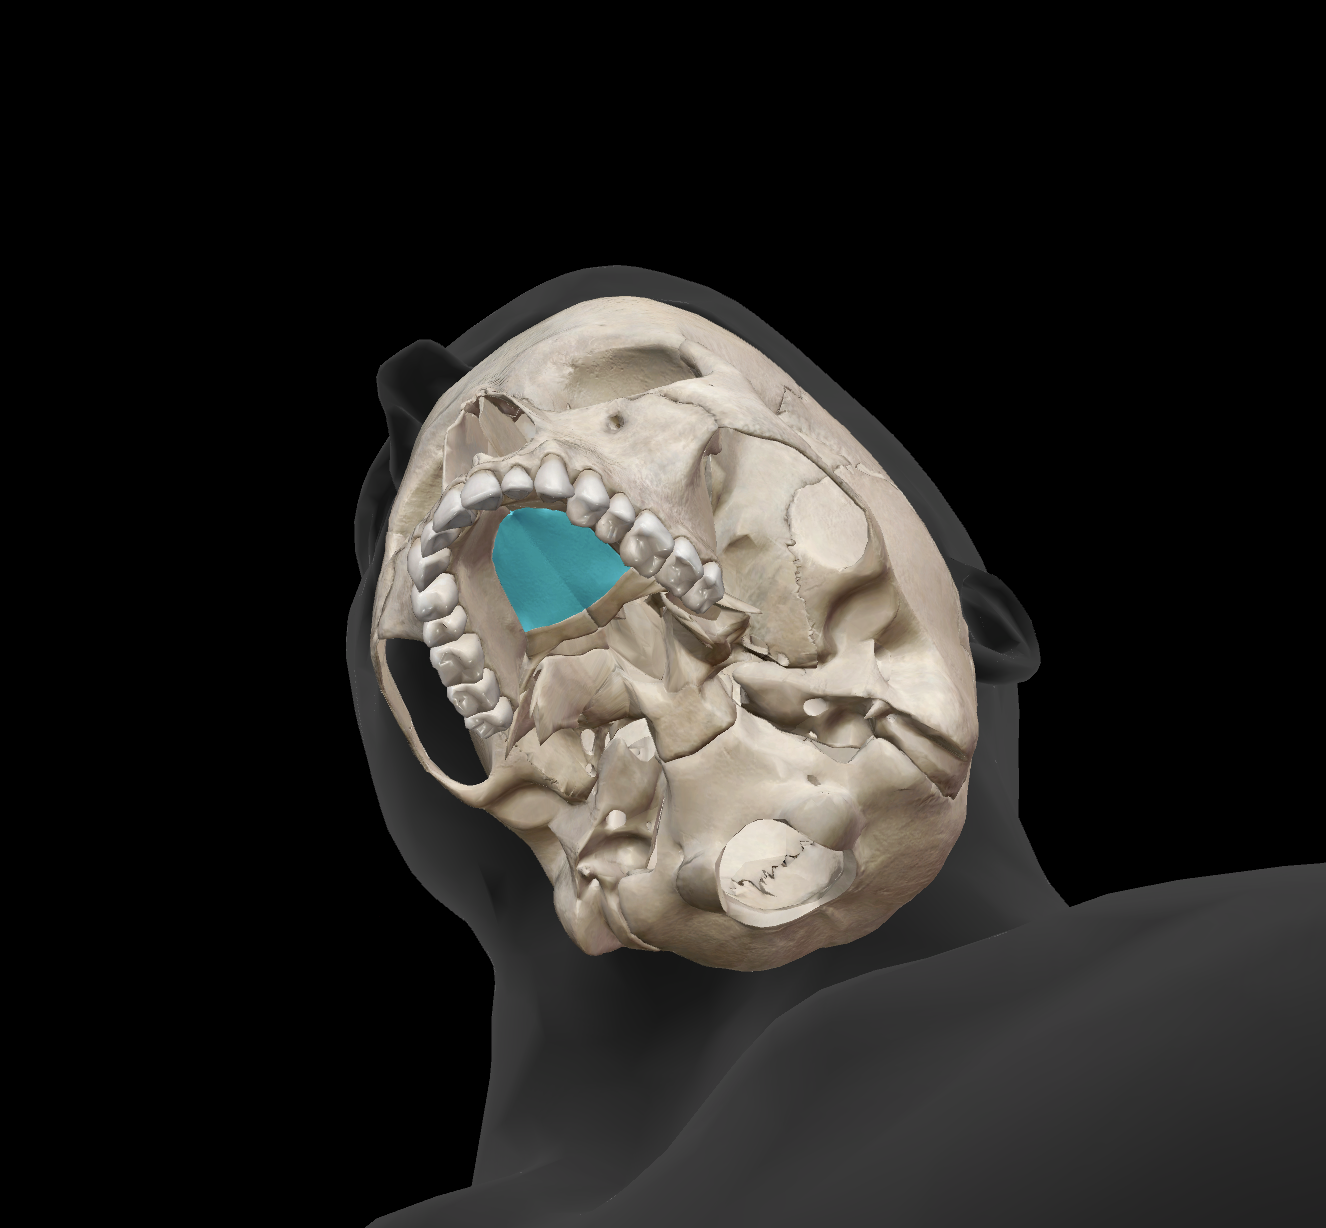

What is the hole called?

foramen magnum

occipital condyles

What is the name of this bone?